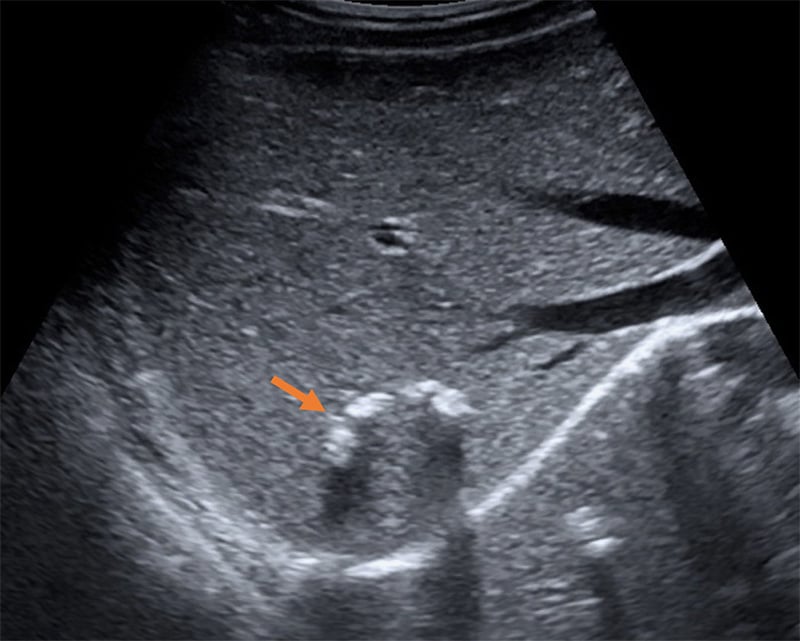

Figure 49. Mild hydronephrosis seen on long axis view of the kidney. Note the mild dilation of the renal pelvis and calyces and the lack of color Doppler flow over the anechoic (black) dilation of the renal pelvis.

Figure 50. Moderate hydronephrosis seen on long axis view of kidney without a change in the thickness of the renal cortex.

Figure 51. Severe hydronephrosis seen on long axis view of the kidney. Note the severe dilation of the renal pelvis and thinning of the renal cortex, as well as the dilated ureter extending to the right of the image.

Figure 52. Moderate hydronephrosis with ureteral dilation (extending deep from the renal pelvis).